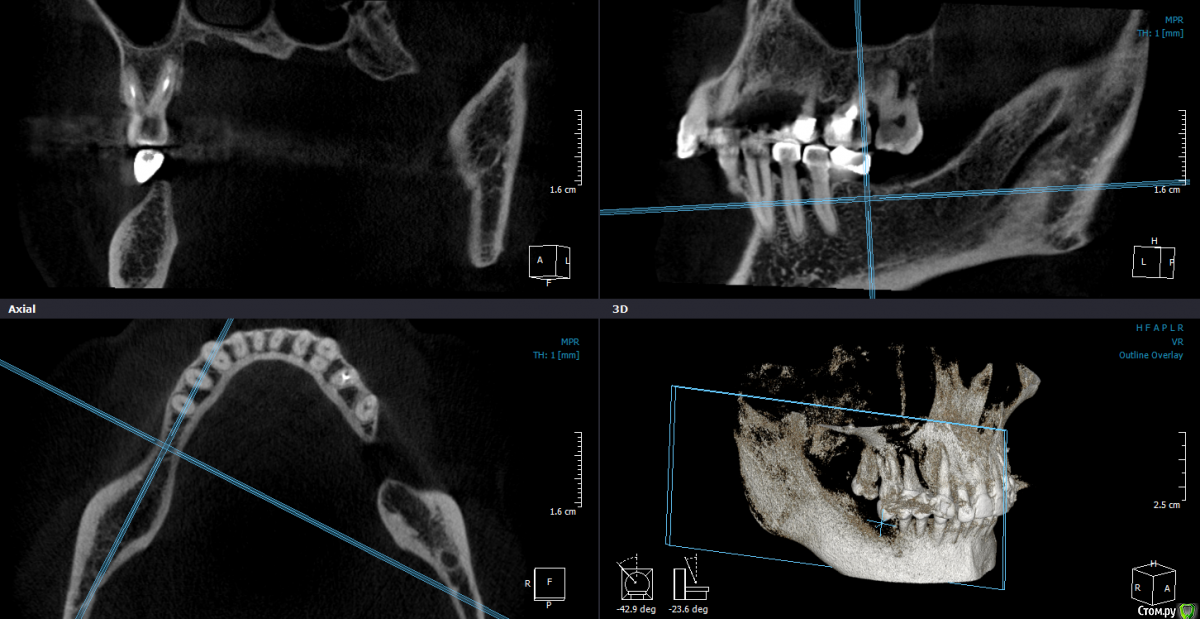

Mane Опубликовано 22 декабря, 2014 Поделиться Опубликовано 22 декабря, 2014 в целом хорошо. но нет деталей где я смогу понять что качественно отработали: 1) кт срезы до и после с замерами чтоб было понятно на сколько нарастили 2)кт срезы с установленными имплантами чтоб было понятно какие болты удалось установить и стало чтоб всем понятно для чего наращивали - ведь вы растили в высоту и в ширину. 3) фото на этапе установленных имплантов - соотношение платформы импланта и уровня кости - заглубили или нет - если да то насколько. Ориентировались ли на будущий зенит зуба. мне понравилось. но чуйка что есть гиперлечение - думаю можно было болты и костную пластику совместить. Растить по высоте я скорее всего бы не стал. 1 Ссылка на комментарий

Dantist55 Опубликовано 22 декабря, 2014 Автор Поделиться Опубликовано 22 декабря, 2014 в целом хорошо. но нет деталей где я смогу понять что качественно отработали: 1) кт срезы до и после с замерами чтоб было понятно на сколько нарастили 2)кт срезы с установленными имплантами чтоб было понятно какие болты удалось установить и стало чтоб всем понятно для чего наращивали - ведь вы растили в высоту и в ширину. 3) фото на этапе установленных имплантов - соотношение платформы импланта и уровня кости - заглубили или нет - если да то насколько. Ориентировались ли на будущий зенит зуба. мне понравилось. но чуйка что есть гиперлечение - думаю можно было болты и костную пластику совместить. Растить по высоте я скорее всего бы не стал.КТ посмотрю позже на работе - я в отпуске.По высоте добавляли чтобы зубы не получились большими.Импланты не заглублял, т.к. у XIVE полированная фаска.Насчет гиперлечения может Вы и правы. Эту работу я сделал сразу после приезда от Кури. 2 Ссылка на комментарий

Dantist55 Опубликовано 22 декабря, 2014 Автор Поделиться Опубликовано 22 декабря, 2014 Мне не понравилось просветление в 3 квадранте. Крутили КТ? Что это?Перед имплантацией крутил-все было норм. Ссылка на комментарий

SDC Опубликовано 22 декабря, 2014 Поделиться Опубликовано 22 декабря, 2014 Через 5 месяцев...Мне не понравилось просветление в 3 квадранте. Крутили КТ? Что это? Ссылка на комментарий